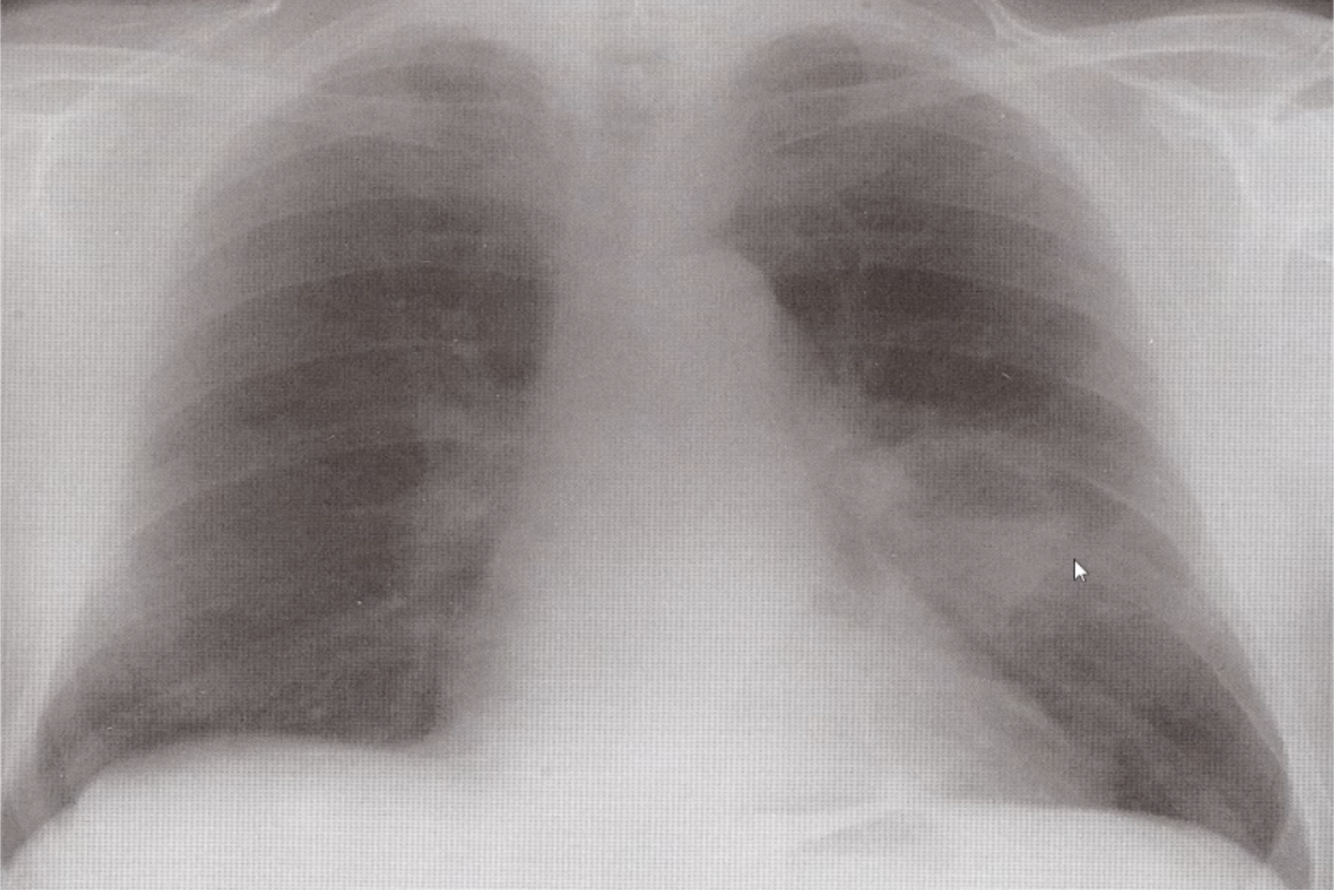

Which diagnosis is suggested by this CXR?

Pneumothorax

No lung markings on affected side

Mediastinum deviated away from the lesion